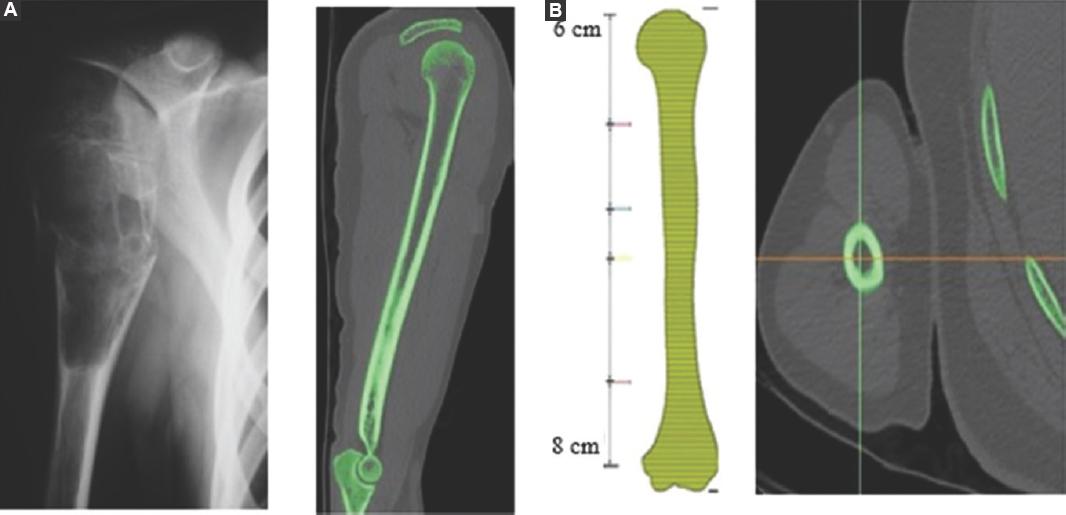

Los pacientes contaron con radiografías convencionales de húmero en posición anteroposterior y lateral para la medición de la longitud y del diámetro de la tumoración por parte del médico, y con TC para la medición de la longitud del húmero sano, así como el canal medular (Fig. 2 A y B).

Figura 2 A: radiografía de húmero con tumoración, obtención de dimensiones de tumores existentes en el Instituto Nacional de Rehabilitación "Luis Guillermo Ibarra Ibarra". B: tomografía computada de húmero sin tumoración de un paciente candidato a prótesis.

Los parámetros de medición de la TC se obtuvieron a partir de 8 cm de la zona distal y 6 cm de la zona proximal, cada 10 cortes a partir de estas. Se diseñaron polilíneas y se crearon curvas (Fig. 3 A y B).